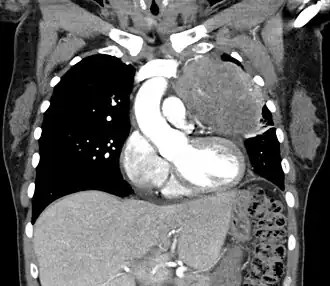

Les thymomes se présentent comme une masse bien définie du médiastin antérieur, proche du péricarde et dans un plan plus antérieur que les gros vaisseaux intrathoraciques (aorte ascendante et sa crosse, artère pulmonaire, veine cave supérieure). La masse peut être sphérique ou lobulée, mais présente un aspect homogène (plus rarement kystique) qui se réhausse après injection et peut contenir des calcifications[29].

Les critères scanographiques d'envahissement local doivent être recherchés car ils guideront le traitement. D'autre part, l'envahissement scanographique est corrélé au pronostic[30]. L'absence d'un liseré graisseux entre la masse et les vaisseaux, notamment l'aorte et la veine cave supérieure, est un signe d'envahissement local. L'ascension d'une coupole diaphragmatique, comme en radiographie thoracique, est un signe d'envahissement du nerf phrénique[31].

L'irrégularité des contours de la tumeur, ainsi que la présence de calcifications, de nécrose ou d'hémorragie intratumorale sont des signes de mauvais pronostic corrélés à des tumeurs plus agressives[32].